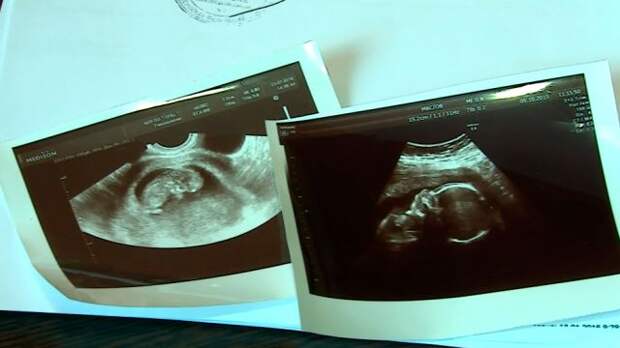

В начале декабря УЗИ показывало, что с плодом все в порядке (фото из архива семьи)

Однако, как выяснилось, это не так. Елена и Андрей Моисеевы живут в самом Орле. Семья у них благополучная, ребенок был желанным. Елена наблюдалась у врачей на всем протяжении беременности. Супруги успели выбрать мальчику имя – Всеволод. Но их родительское счастье длилось всего три дня.